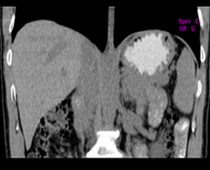

患者,男,57,常年不吃午饭,近一个月来腹部隐痛,无明显黄疸,明天进行增强扫描,图象另上传,麻烦各位帮忙一起看看讨论讨论

肝外胆管扩张,胰头增大,肠系膜上静脉似有包埋征象。

考虑:胰头占位性病变,建议增强进一步检查。

肝外胆管扩张,胰头增大,占位性病变可能性大.

肝外胆管稍扩张,胰腺钩突略增大,但外形尚可,境界清楚。(常年不吃午饭)提示胰腺炎可能大,肿瘤第二步考虑。

支持考胰头占位性病变,感觉十二指肠壁不规则增厚,不排除十二指肠降部占位可炎症

胰头增大,考虑胰头占位性病变。

胰头增大,胆总管增宽,考虑胰头癌可能性大,明天看增强片有助诊断.